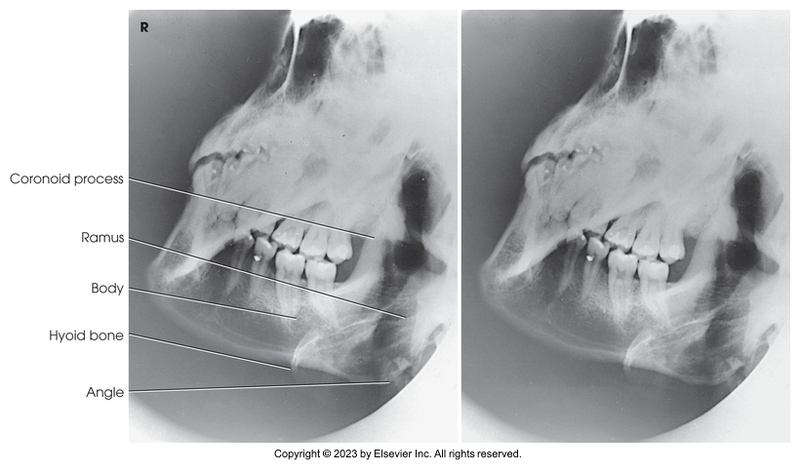

Axiolateral of mandibular rami

Axiolateral oblique of the mandibular body

Axiolateral of mandibular ramus

Axiolateral oblique of mandibular body